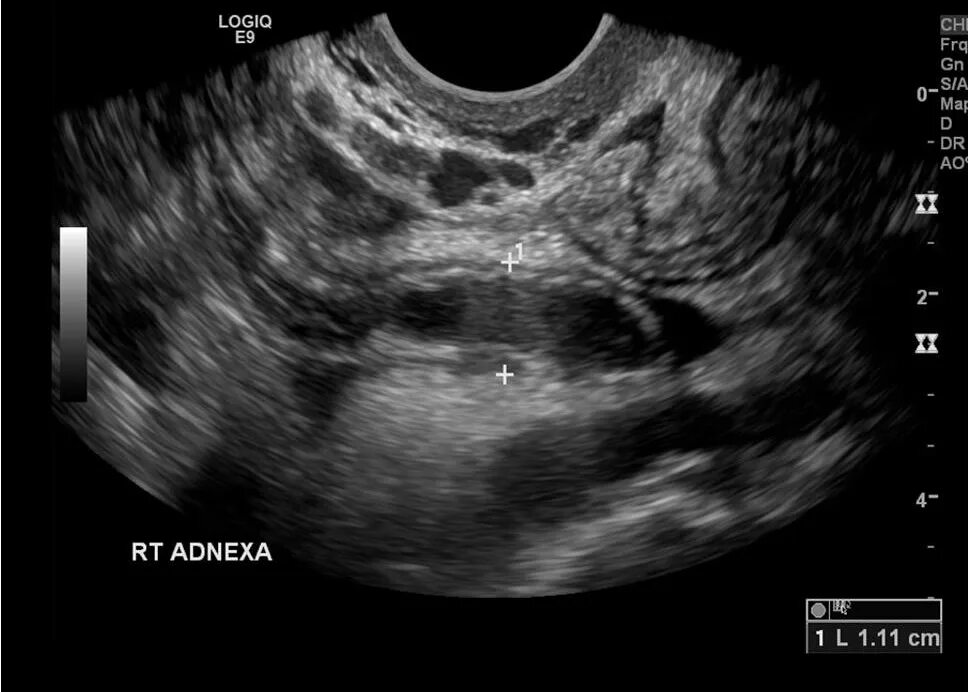

Аппендицит на узи можно ли